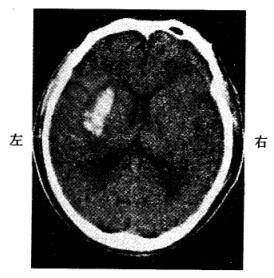

问题 男,52岁。清晨锻炼时觉头痛、左侧肢体麻木和乏力。有高血压病史。半天后到急诊就诊。查体:嗜睡,右侧肢体肌力3级,腱反射高于左侧,右侧Babinski征阳性。脑CT见图示:

患者可能诊断为

选项 A:脑血栓形成 B:高血压性脑出血 C:短暂性脑缺血发作 D:脑栓塞 E:脑转移癌

答案 B

解析 本题考查目的是综合临床资料、CT图像作出脑血管病的诊断。本病例为急性起病的脑血管病。脑血管病分为缺血性卒中和出血性卒中。脑血栓形成、短暂性脑缺血发作、脑栓塞均为缺血性卒中范畴。高血压性脑出血为出血性卒中。根据脑缺血性卒中和出血性卒中的鉴别诊断表(表1-2),可以得出正确答案为B。脑转移癌起病较慢,而且CT的病灶周围有大片水肿,为迷惑答案。